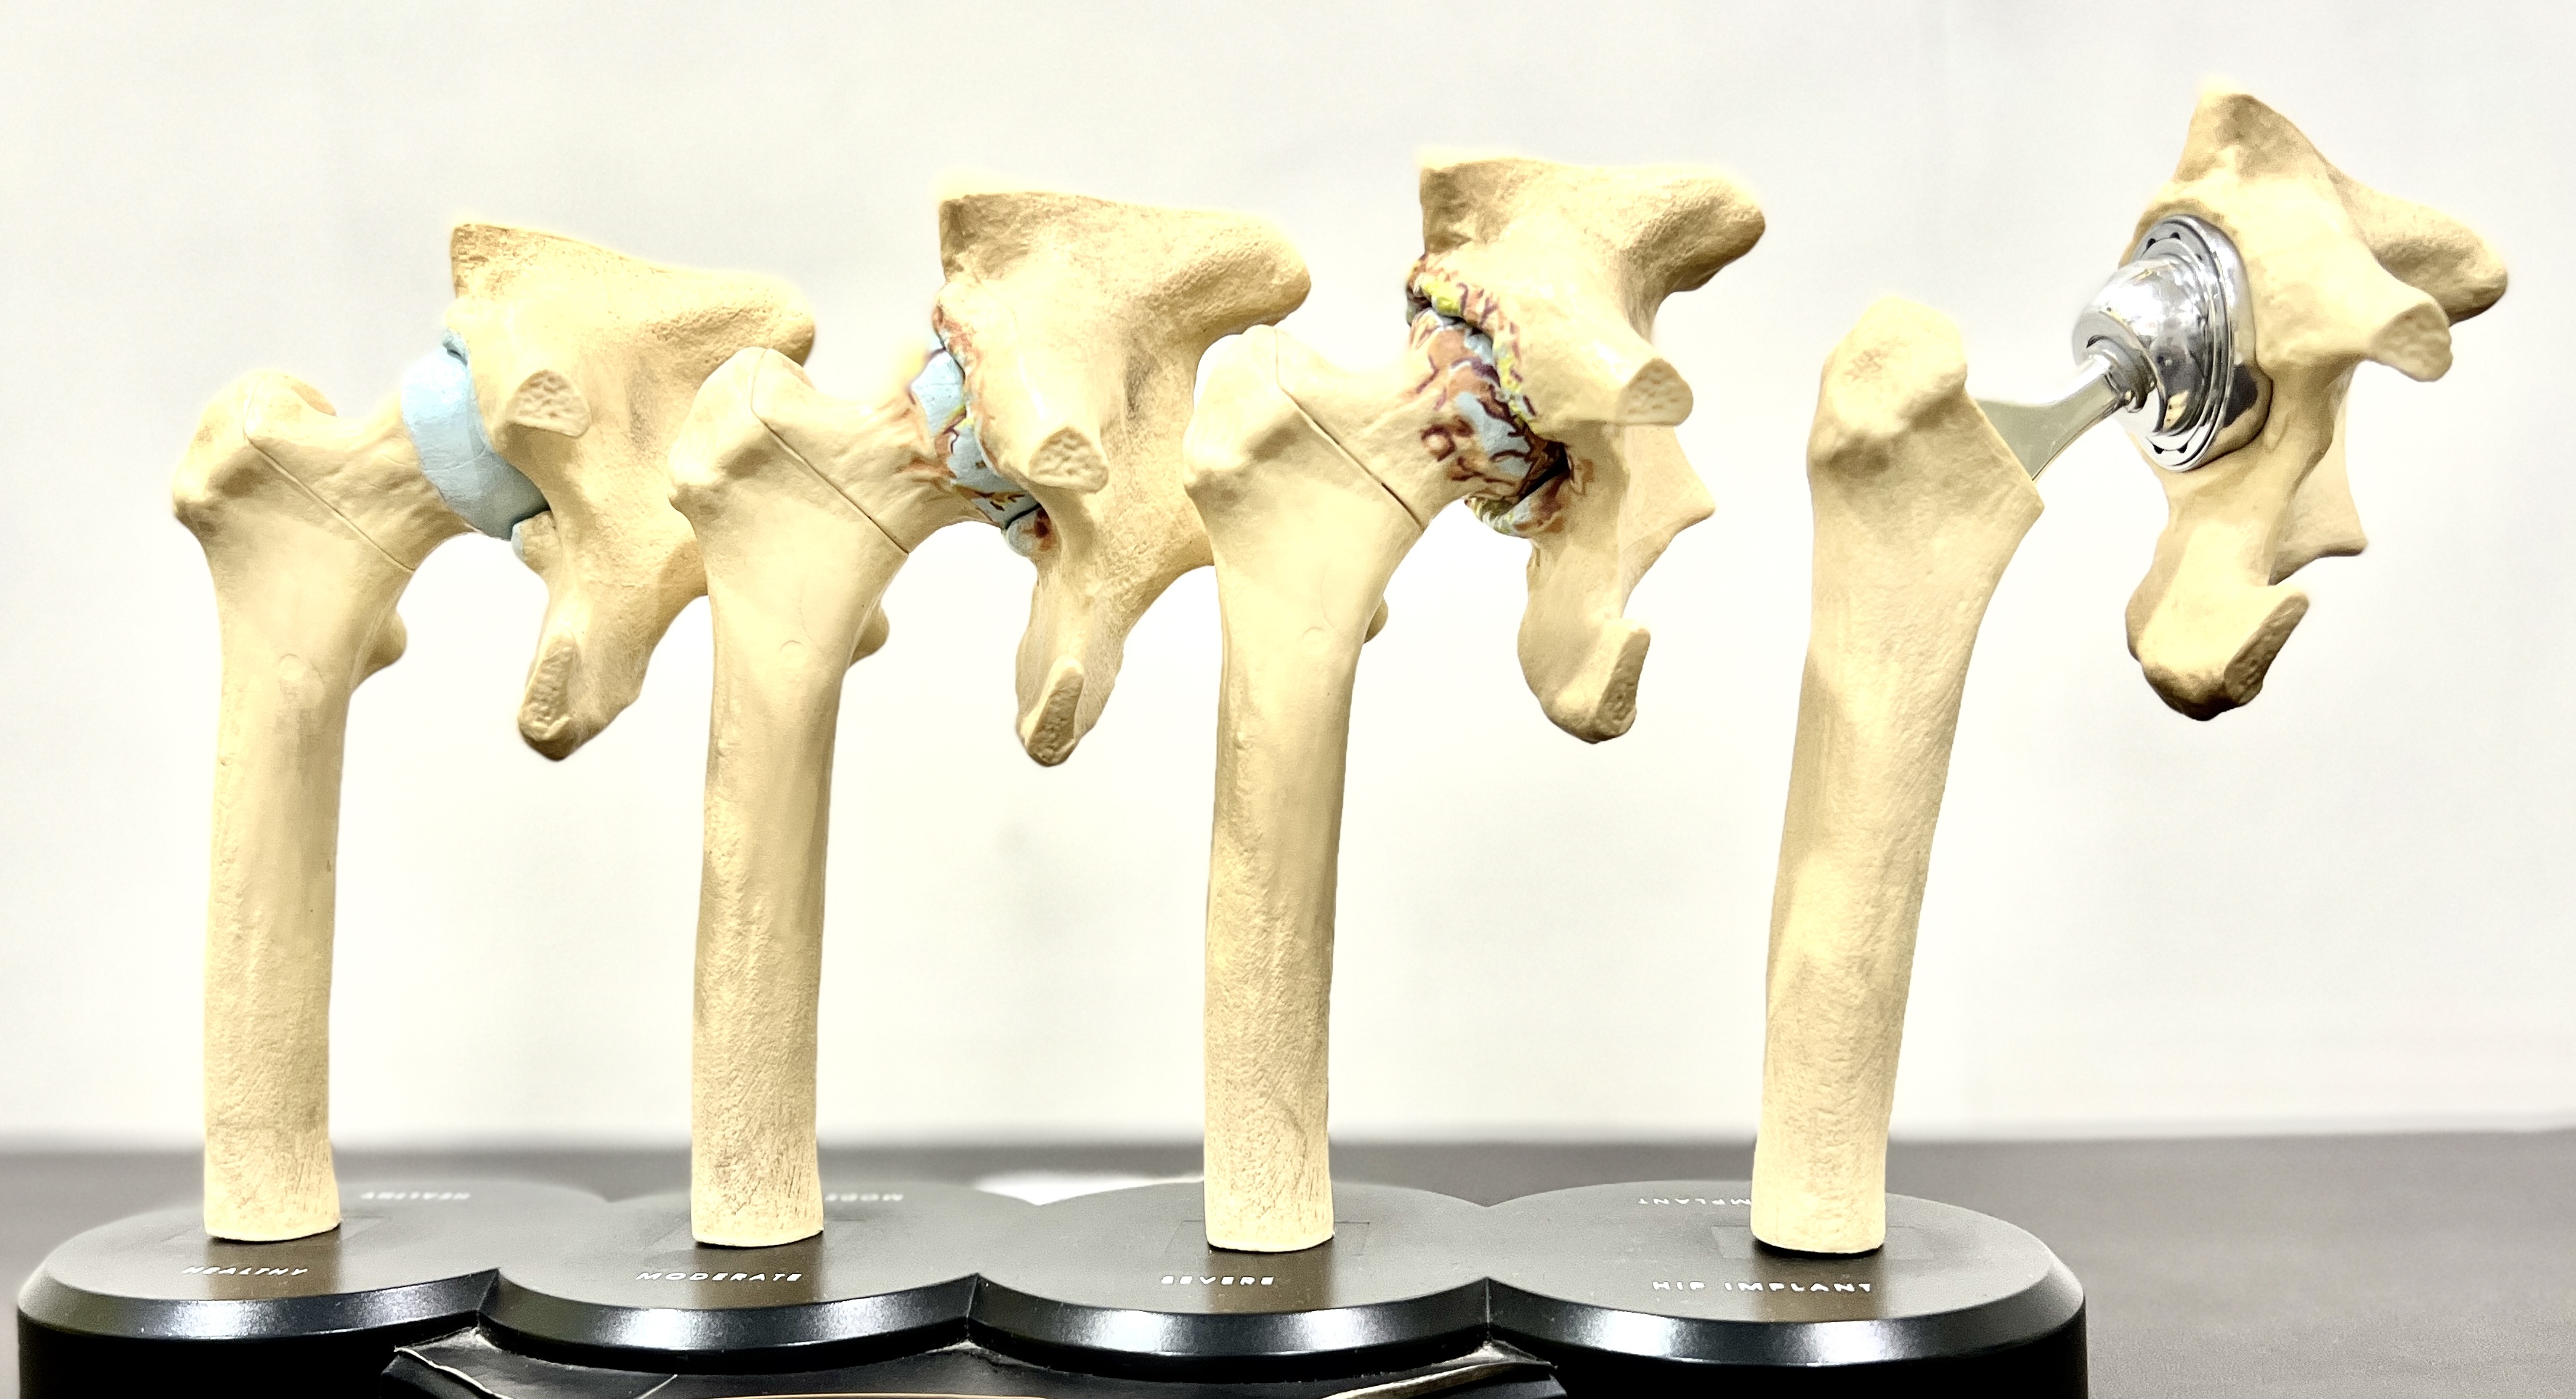

Total Hip replacement surgery is a surgery in which the worn out or damaged surface of the hip joint is replaced with prosthetic artificial surface made up of special metals like ceramic, chromium-cobalt, oxinium, titanium or polyethylene. The aim of this surgical procedure is to relieve you of your pain, deformity and swelling. So that you can get back to your active life. Now, that you have been suggested surgery, we help you plan and go for it.